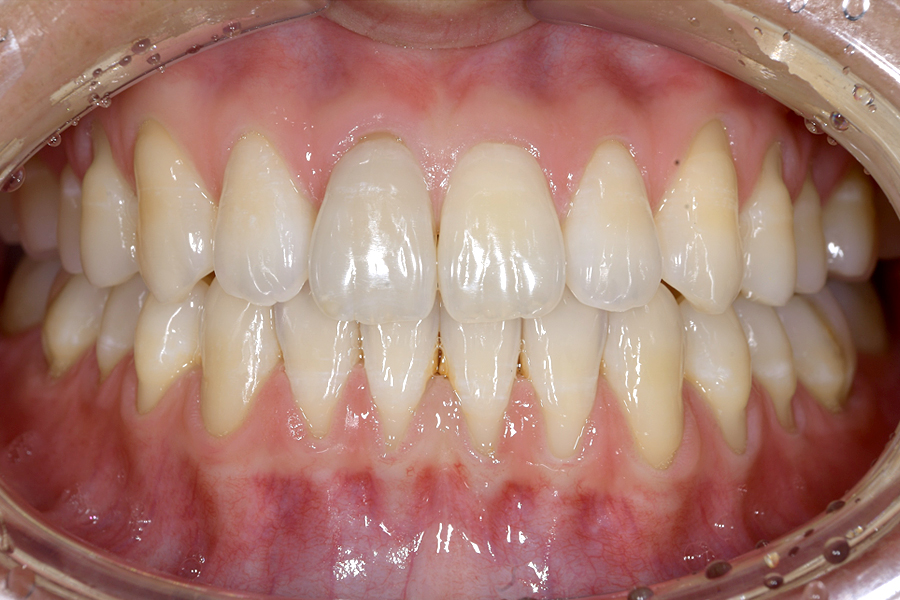

| 主訴 | 見た目を治したい、歯を白くしたい |

|---|---|

| 治療期間 | 1年6か月 |

| 治療費 | マウスピース矯正と ホームホワイトニングセット 1,022,350円(税込) |

| 治療内容 | 目立ちにくいマウスピース矯正 (非抜歯矯正) 歯と歯の間に隙間をつくることにより、歯列弓を広げながら治療を行いました。 また矯正用マウスピースをトレー代わりにし、ジェルを入れてホームホワイトニングを同時に行っております。 |

| 治療のリスク | ・後戻りする可能性があるのでリテーナーを最低でも矯正期間以上はつける必要があります。 ・ホワイトニング後、一時的に痛みが出る場合があります。 |